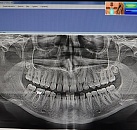

Панорамный снимок

- Показывает полную картину состояния зубов и костной ткани.

- Не требует подготовки, занимает всего 2-3 минуты.

- Обеспечивает высокое качество изображения при минимальном уровне излучения.